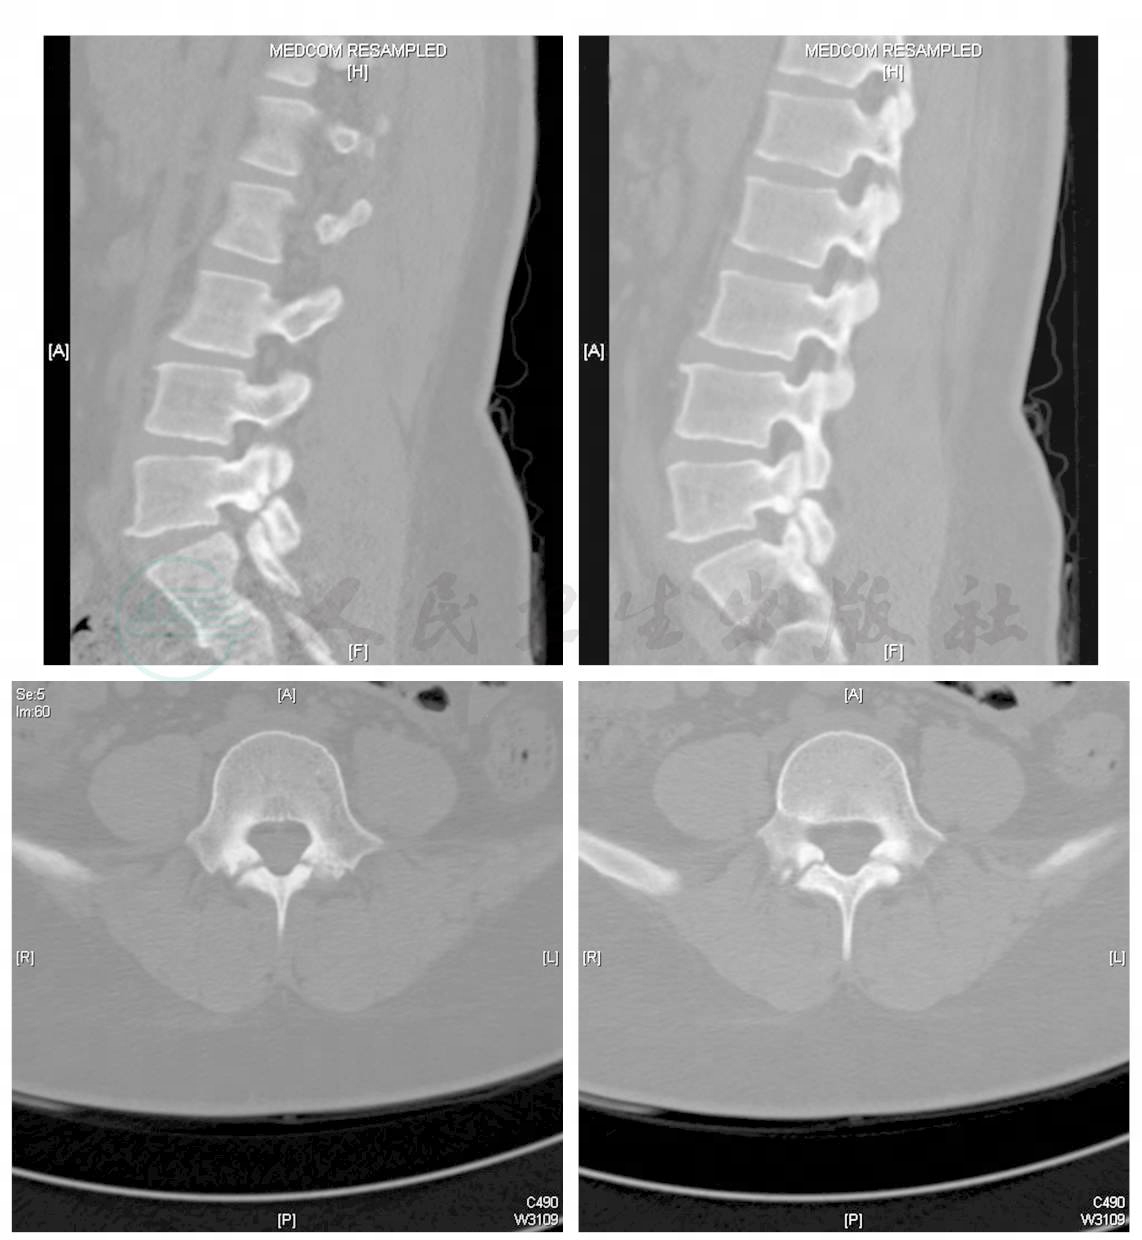

腰椎滑脱是指腰椎椎体序列变得不整齐,腰椎椎体可以向前或向后移位的一种神经外科常见病以下是关于腰椎滑脱的详细解释定义与表现腰椎滑脱通过侧位X线检查可以观察到,主要表现为腰椎椎体在序列上不再保持整齐,而是出现向前或向后的移位这种移位可能导致椎管狭窄,进而压迫神经,引发一系列临床症状,如。